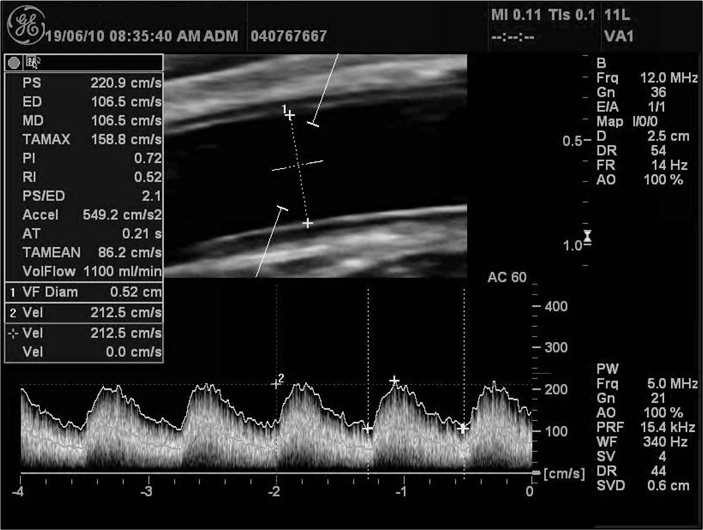

투석혈관 초음파 및 투석혈관 조영술로 정확한 진단에서부터 좁아진 투석혈관(협착)의 풍선확장술(PTA, Percutaneous Transluminal Angioplasty), 막힌 투석혈관의 혈전제거술(Thrombectomy), 투석 도관 삽입(Perm. Cath insertion)까지 환자분의 투석 혈관을 위한 모든 시술을 시행합니다.